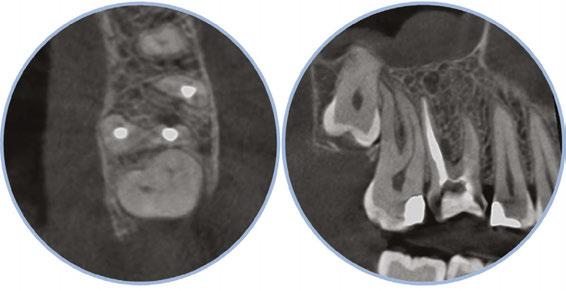

Figure 3: Second maxillary molar with external root resorption (ERR) with incidentally captured ERR on the lower mandibular first molar as well. When there is one tooth with resorption, be suspicious of other teeth with resorption, especially on younger patients Figure 6: No PARL on PA film. Clear PARL on scan taken with medicament Figures 4 and 5: 4. Mandibular molar with a J-shaped lesion due to endo — not a vertical root fracture. Path of least resistance happens to be through a distal perio pocket, but this is an endo-perio lesion and not a VRF. Incidentally, a mucous retention cyst was captured in the sinus. 5. Healing after bridge removal and retreatment

a realistic prognosis. Unfortunately, not all teeth can be saved. Some are not candidates for retreatment (Figure 11). Without a CBCT scan, it would be easy to attempt these retreatments only to discover the true problem mid-treatment, or worse — to think I had caused one (Figures 10 and 11). This added information not only helps the practitioner, but also provides patients a higher level of confidence and trust in you.

With retreatments, maybe the root canal looks completely fine on a PA or panoramic x-ray, but the patient says that it just doesn’t feel right. A cone beam can often reveal the cause of the patient’s discomfort. This could be that the tooth was perforated, cracked or has an unfilled canal, and the patient is totally justified in feeling like something’s wrong. Or sometimes the scan will show that there is another issue on an adjacent tooth or in the patient’s sinuses (causing their discomfort). When patients sense a problem but are told that there is not one (usually based on 2D radiographs), that’s not a great feeling. Being able to show the patient the CBCT scan and say, “You were right, and here’s the issue,” improves the patient experience.

I also see a good amount of resorption cases. Without the scan, I can’t determine how large or destructive the lesion is. I cannot accurately determine the best course for these resorptive cases without knowing what they look like in 3D (Figure 3). I might approach it surgically without endo, or I might plan only for the endo and monitor it after. And, some cases need both at

the same time, or closely planned together, or a resorptive defect could be taken care of internally with the endo — all of that thought and planning comes from the scan; usually not possible with 2D imaging alone.